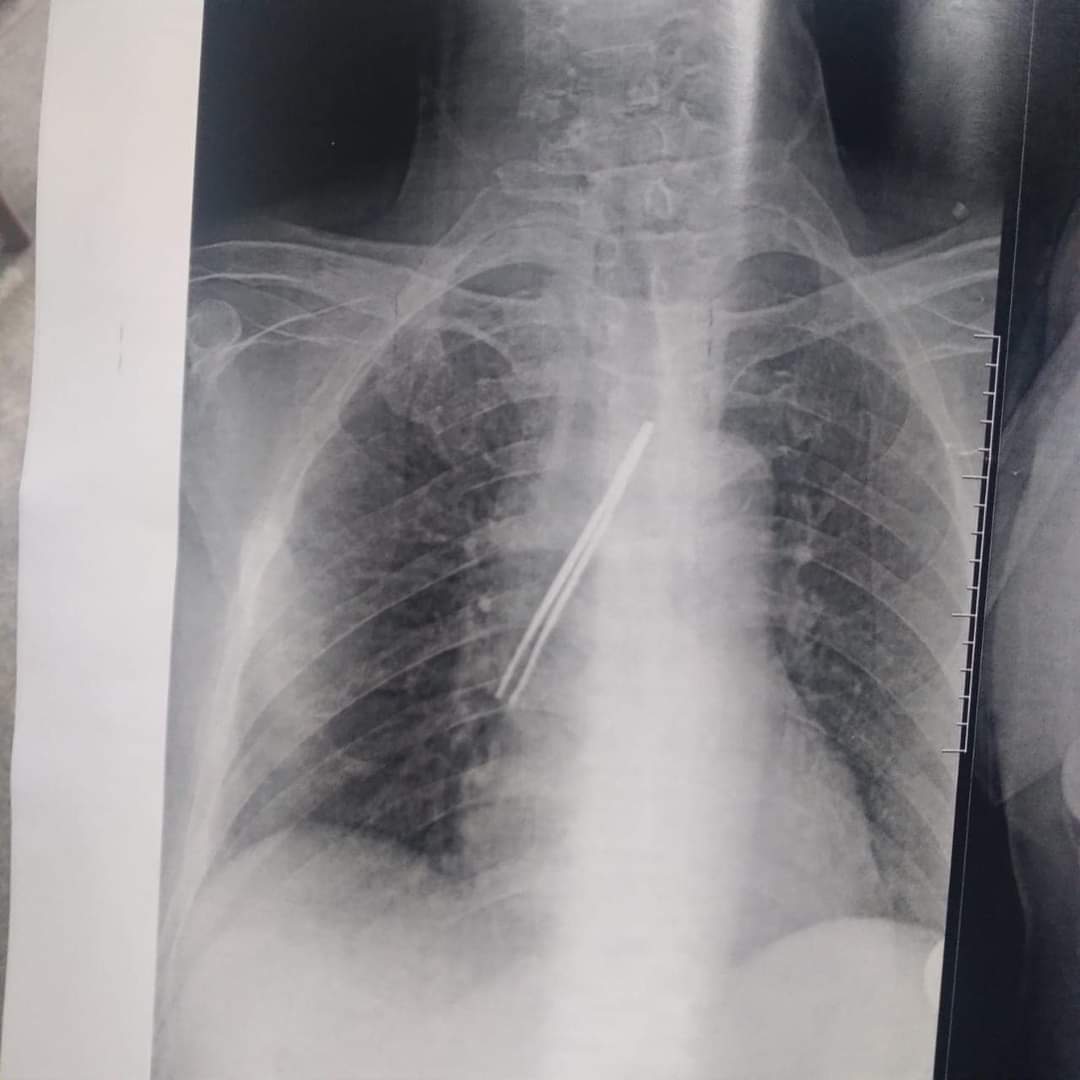

استخراج "ملقاط شعر" من القصبة الهوائية لمريض بمستشفى بنها الجامعي

نجح فريق جراحي بقسم جراحة القلب والصدر بمستشفى بنها الجامعي بمحافظة القليوبية، في استخراج "ملقاط شعر"، من القصبة الهوائية لمريض يعاني من شق حنجري قديم، وأثناء قيامه بتنظيف فتحة الشق الحنجري بطريقة غير طبية وغير صحيحة باستخدام الملقاط ملفوف بمناديل ورقية، سقط منه وابتلعه ودخل لفتحة القصبة الهوائية.

وأوضحت مستشفى بنها الجامعي، فى بيان له، أنه جرى الآن استخراج "ملقاط شعر" من القصبة الهوائية لمريض يعاني من شق حنجري قديم، وبينما يقوم بتنظيف فتحة الشق الحنجري بطريقة غير طبية وغير صحيحة باستخدام ملقاط ملفوف بمناديل ورقية اتشفط منه الملقاط ودخل لفتحة القصبة الهوائية.

وتابعت المستشفى، أنه حضر المريض للقسم في حالة اختناق، وتم دخوله العمليات فورا، حيث نجح الدكتور باسم مفرح الأستاذ المساعد بالقسم، وبمعاونة الدكتور أحمد الخضري مدرس مساعد التخدير، من استخراج "الملقاط"، وخرج المريض بسلامة الله من العمليات ويخضع لاستكمال علاجه بالقسم لحين تماثله الكامل للشفاء.